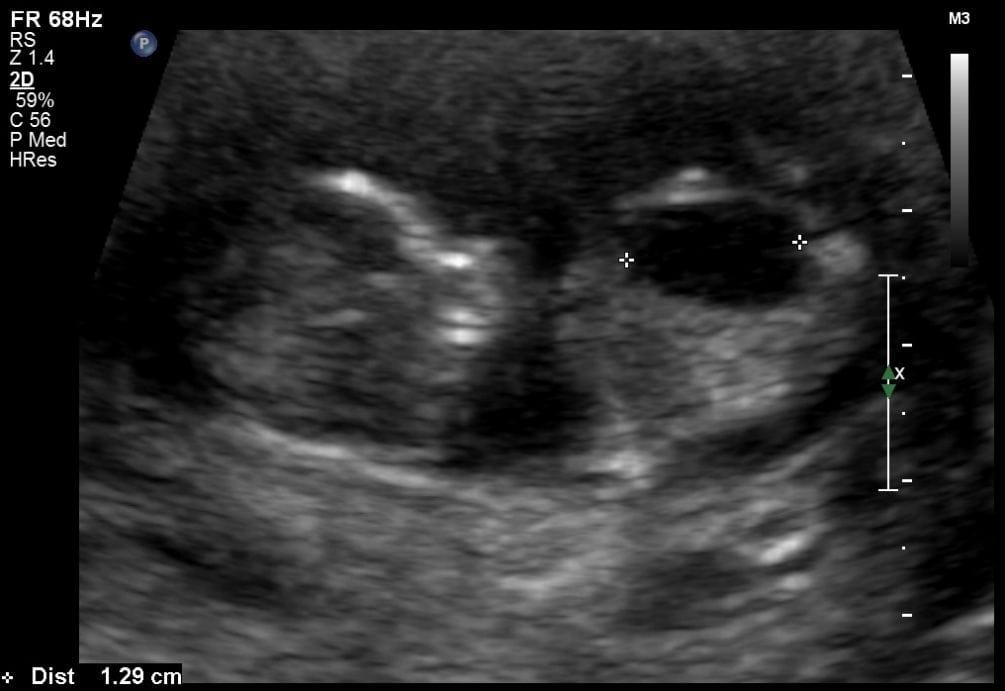

This course offers a comprehensive overview of the sonographic diagnosis of fetal uropathy, focusing on identifying obstructive abnormalities of the urinary tract through prenatal ultrasound. Learn about key diagnostic markers, including pyelectasis, hydronephrosis, ureteropelvic junction obstruction, and lower urinary tract obstruction, as well as their clinical implications. The course also covers management options, from conservative monitoring to in-utero interventions like vesico-amniotic shunting, and explores the prognosis for conditions such as congenital megalourethra and renal dysplasia.

Describe the sonographic findings with pyelectasis, ureteropelvic junction obstruction, hydroureter and lower urinary tract obstruction.